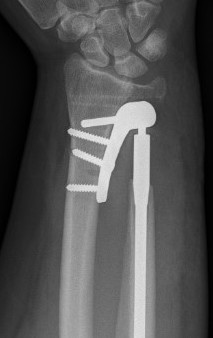

Darrach's procedure / distal ulna excision

Indication

Elderly / low demand patients

Technique

Dorsal approach

- between ECU and EDM (extensor compartment 5 and 6)

- protect dorsal sensory branch of ulna nerve

- open extensor compartment

- open capsule

- resect distal 2cm of the ulna

- careful to close capsule under extensor tendons as tendon rupture is known complication